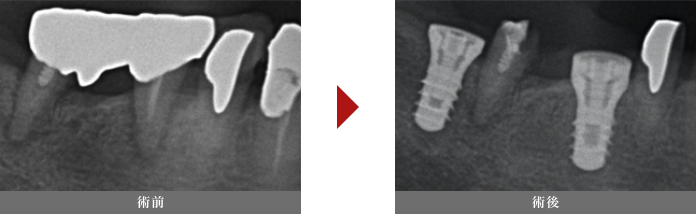

腫れない痛くない抜歯即時埋入法(抜歯からインプラント埋入まで約30分)

抜歯即時埋入とは

インプラント治療は待機時間が非常に長いです。抜歯後2~6ヶ月経過し、インプラント手術から1~3ヶ月程待ちます。

一般的には抜歯をしてから仮歯が入るまでは9ヶ月くらいの医院が多いと思います。

通常保存不可能な歯は感染を起こしていることがほとんどで、感染組織を残しているとインプラントと骨の結合を阻害してしまいます。

そして抜歯後4ヶ月程で抜歯窩は骨に置き換わっていきますが、それより前にインプラント手術を行ってしまうと、

穴がボコッとあいたところにインプラントを埋めることになり、手術の難易度が上がってしまい、対応できない歯科医師が多いです。

そのため、手術が簡単になる抜歯後4ヶ月程で手術を行う治療が一般的です。なかには全ての症例で抜歯後6ヶ月待つ歯科医院もあります。

しかし近年の論文や文献で適切に抜歯窩を綺麗にしていれば

抜歯してそのままインプラントを埋めることも問題ないと証明されてきており、当院でも積極的に採用しております。

やはり一番のメリットは腫れにくい痛みにくいことです。

デメリットは、抜歯窩にインプラントを入れるため、治癒した骨よりも手技が難しく、様々な知識を必要とする手術の難易度が高いことです。

そのため、経験豊富な専門医が行うことが望ましいと考えています。当院では、腫れない痛みにくい抜歯即時インプラントを多くの患者様に行っております。

症例

70代女性

治療回数:1回

治療費:追加費用は頂いていません

リスク:通常の手術と比べ、約3%程成功率が下がると考えられています。(通常は98%の成功率)